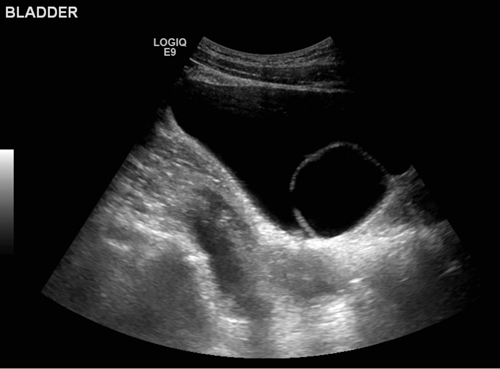

A 39-year-old female presented with recurrent urinary tract infection and underwent ultrasound of the renal tract and bladder.

1. Describe the findings.

2. What is the differential diagnosis?

3. What appearance might you see in the upper tracts?

Case 1

- There is a well-defined, curvilinear structure seen within the urinary bladder, which contains fluid.

- This appearance could be due to a Foley catheter, foreign body or ureterocele.

- If the ureterocele is large, the kidney may be hydronephrotic and the ureter dilated all the way down to the bladder. The CTU image below from the same patient demonstrates the ureterocele, and the left kidney is markedly hydronephrotic with hydroureter down to the bladder.Ureteroceles are associated with duplex kidneys, so it is important to assess the affected kidney to ascertain if there are one or two ureters.